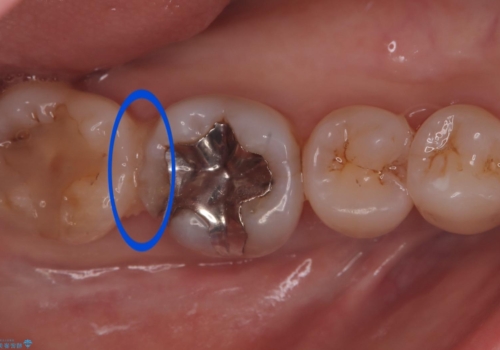

歯間に食渣がつまるのをどうにかしたいとの主訴のもと、治療を開始しました。フロスを通してみると、コンタクトは無く0.25mm程のスペースがありました。

メタルインレーを歯冠色のものに変えたいという希望もあったため、セラミックインレーでのやり替えによるコンタクトの再現をしています。

また、近心側にう蝕が認められたため窩洞の範囲を元々入っていたメタルインレー窩洞よりも広げています。